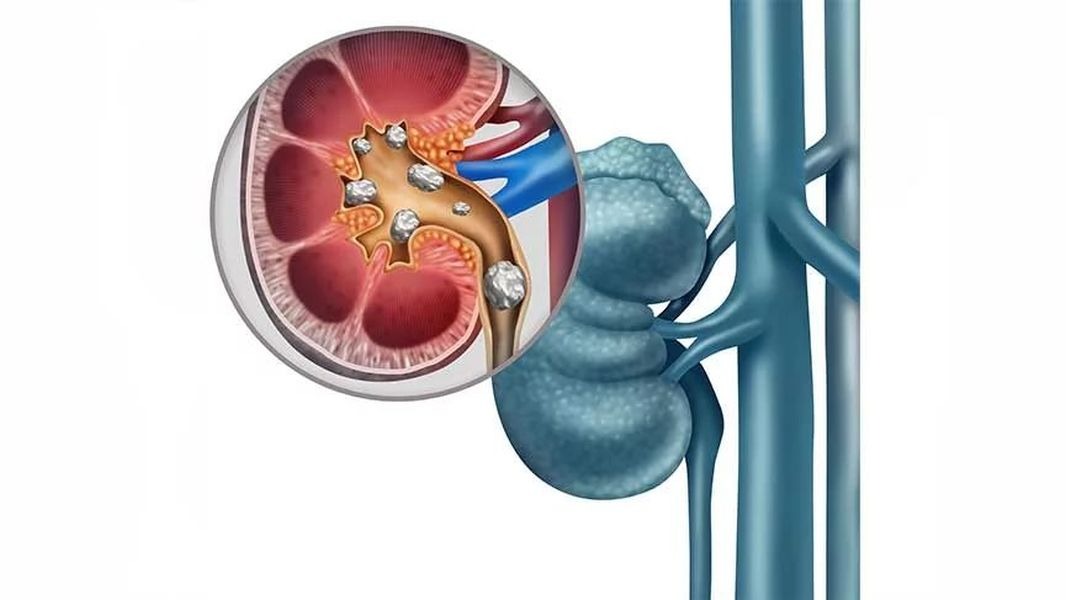

Kidney Stone Specialist in Castle Mill Thane -----...

Kidney Stone Specialist in Castle Mill Thane ------------------------------------- Kidney stones are solid mineral deposits that form in the urinary tract and can cause sharp pain, difficulty urinating, and blood in the urine. When not treated on time, they may lead to serious infections or kidney damage. That’s why consulting an experienced kidney stone specialist is crucial for accurate diagnosis, effective treatment, and long-term relief. GMB ID https://maps.app.goo.gl/vpQDUk7ZjmiCJMtP7 Email dr.ankur.bhanushali@gmail.com Website https://www.drankurbhanushali.com/ Website https://aayushhospital.co.in/ Google Map https://maps.app.goo.gl/1afYdjdiDBKKjDFQ7 Website: https://bestsurgeoninthane.com Go to GMB: https://maps.app.goo.gl/XmmGNbgFyhGcqfvV6 In Thane, Dr. Ankur Bhanushali is recognized as a leading kidney stone specialist, offering advanced and minimally invasive treatments to remove stones safely and efficiently. With years of experience in managing complex kidney stone cases, he uses the latest technology including laser lithotripsy, ureteroscopy, and laparoscopic stone removal to provide quick and effective results. Dr. Bhanushali follows a patient-centric approach—beginning with a detailed evaluation, accurate imaging, and a clear explanation of treatment options. Whether your condition requires medication or surgical intervention, he ensures personalized care that prioritizes safety and recovery. His clinic in Thane is equipped with modern urological technology and maintains the highest safety and hygiene standards. Patients value his honest communication, compassionate guidance, and commitment to their comfort throughout the treatment process. Business name Dr. Ankur Bhanushali, Best Laser & Laparoscopic Surgeon, Appendix, Hernia, Gallbladder Stone, Piles Fistula Doctor in Thane Label डॉ. अंकुर भानुशाली, सर्वोत्कृष्ट लेसर आणि लॅपरोस्कोपिक सर्जन, अपेंडिक्स, हर्निया, पित्ताशयाचा खडा, पायल्स फिस्टुलासाठी , ठाणेमधील बेस्ट डॉक्टर Address 1st Floor, Aayush Multispecialty Hospital, Marigold Apt, Almeda Rd, opposite Nitin co. & Honda showroom, Namdeo Vadi, Panch Pakhdi, Thane West, Thane, Maharashtra 400602 Phone no 086910 33033